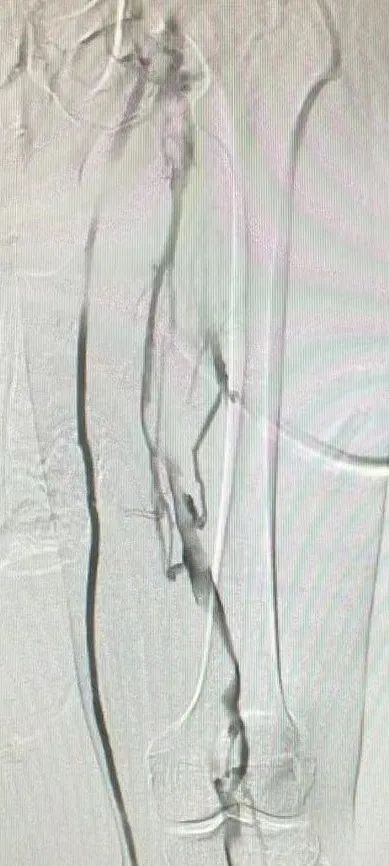

▲术前造影

滤器内有血栓